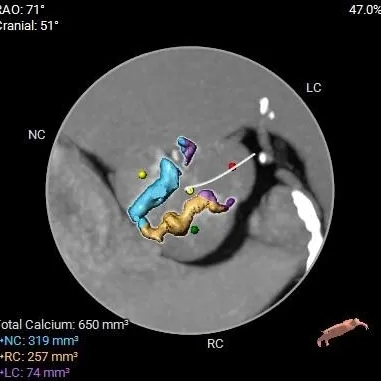

HU598:1225mm3

HU850:650mm3

Type1二叶式主动脉瓣(L-R),瓣叶增厚,极重度钙化,主要分布于无冠窦及右冠窦瓣叶,LVOT偏直筒型;